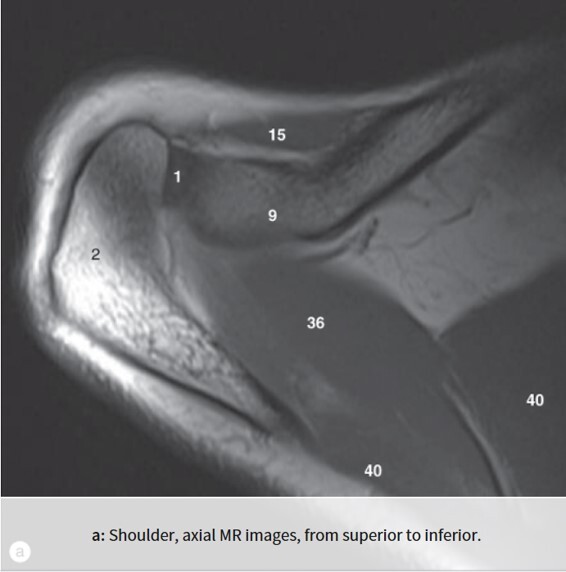

Label 1,2,9,15,36,40

1=Rt. AC joint

2=Rt. Acromion of scapula

9=Rt. Clavicle (acromial end)

15=Rt. deltoid muscle

36-Rt. supraspinatous muscle

40=Rt. trapezius muscle